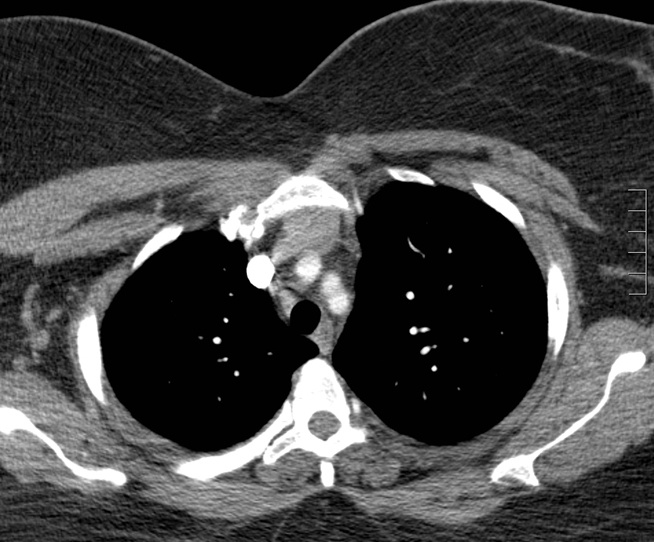

thymoma

CNS Malignancy Treatment

Chemotherapy may be coupled with surgical resection and radiation in patients with highly malignant primary brain tumors (eg, glioblastoma multiforme, medulloblastoma). It can also be considered in patients with highly chemosensitive metastatic brain disease (eg, due to testicular germ cell tumor).

Whole brain radiation is not indicated for the treatment of meningioma; rather, it is usually considered for the treatment of diffuse metastatic brain disease. Focused tumor radiation (stereotactic radiosurgery) may be considered for partially resected or unresectable meningiomas.